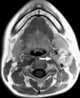

Carotid body tumor

A paraganglioma is a rare neuroendocrine neoplasm that may develop at various body sites (including the head, neck, thorax and abdomen). When the same type of tumor is found in the adrenal gland, they are referred to as a pheochromocytoma. [Source: Wikipedia ]